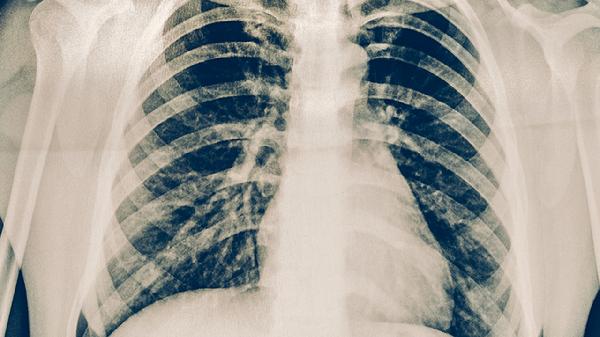

肺结核患者需严格遵循早期、联合、适量、规律、全程的用药原则,治疗期间保持高蛋白饮食如鸡蛋、鱼肉,适当补充维生素B族和维生素C。避免吸烟饮酒,注意室内通风消毒,定期复查胸部影像学和痰菌检查。出现药物不良反应时应及时就医调整方案,不可自行停药或更改剂量。